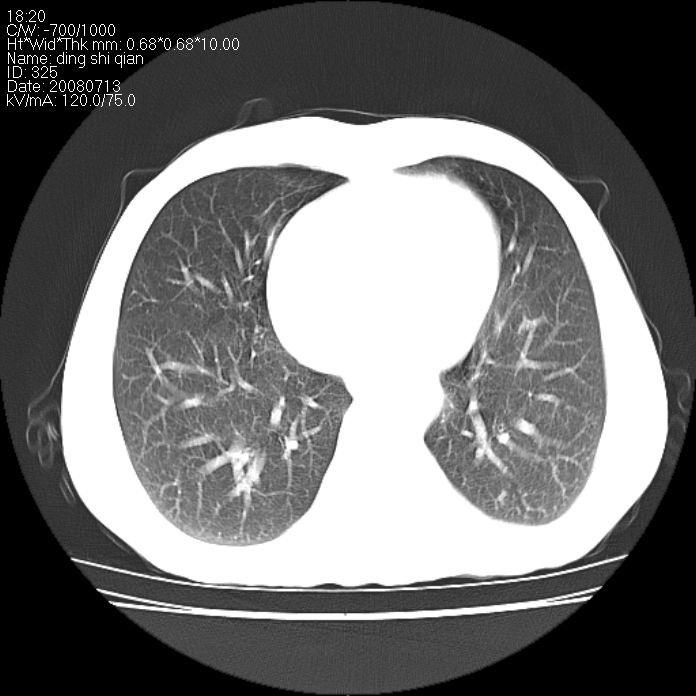

标题: CT14654:男 50岁 近来胸痛 [打印本页]

标题: CT14654:男 50岁 近来胸痛

右侧上肺块状软组织影,浅分叶,边缘毛刺证,与胸膜粘连,考虑:周围性肺癌

右肺上叶周围型肺癌可能性大。

典型右肺周围型肺癌